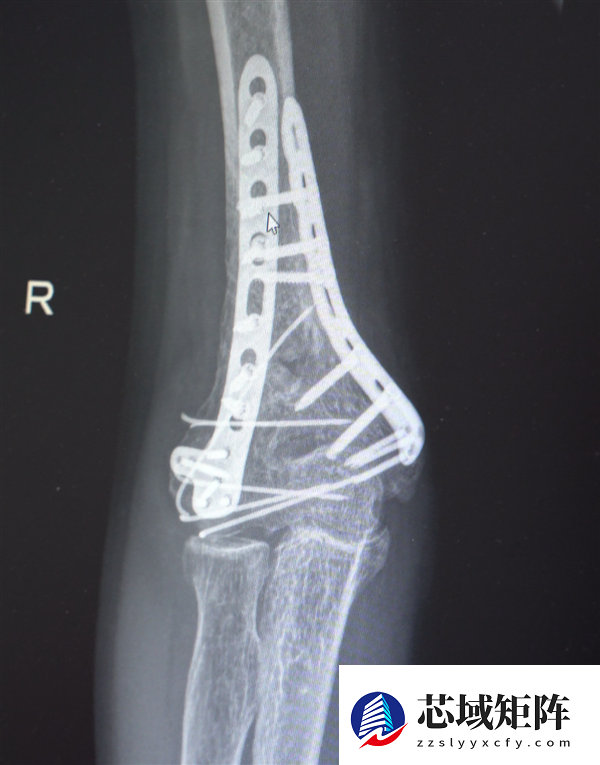

鉴于男子多处骨折,其中最严重的当属右肘部C3型粉碎性骨折,关节面及髁上严重粉碎(碎成了七块),肘关节易粘连,复位固定难度极高。

最终医疗团队采用了“拼古董”式复位固定技术,就像修复一件珍贵的古董瓷器,先拼接大块骨块再贴合小块,先后进行了两次手术。

部分手术后拍摄的影像